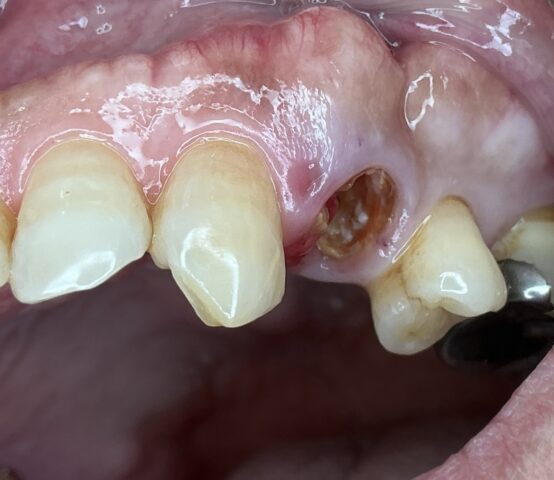

BEFORE

AFTER

左上が咬むと痛い

左上破折のため抜歯してインプラント処置

抜歯時即時にインプラントを埋入。

1回法で処置することで1回の外科処置で短期間で補綴を入れることができた。

抜歯後即時埋入時 術後2週間後 補綴完成時